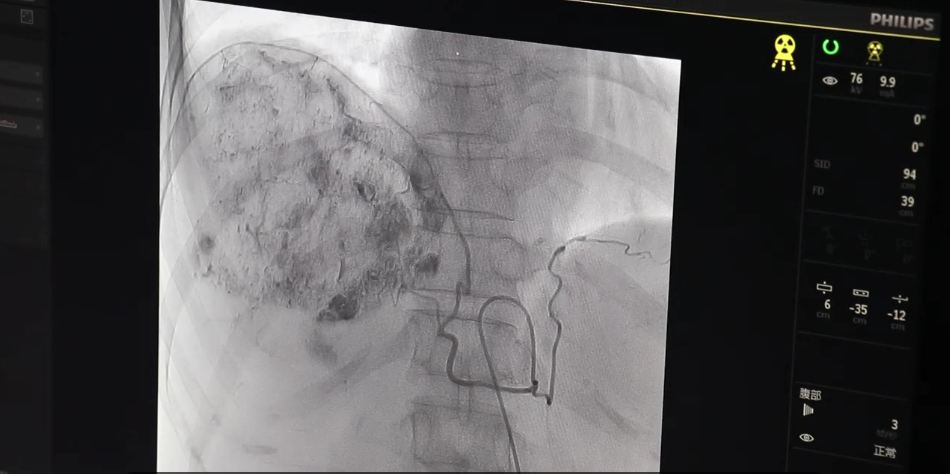

梁女士,66岁,是一位肝硬化并巨块型肝癌患者,发现时肝内肿物已有近10cm大小,甲胎蛋白显著升高。患者短期内消瘦明显,心情低落,几乎丧失了治疗的信心,家属也万分着急。肿瘤科李颖主任带领科室医护人员依托总院介入团队,在进行综合评估后,给患者进行了肝动脉栓塞及灌注化疗。这种精准化介入治疗既可以增加局部抗肿瘤治疗的力度,又可以阻断肿瘤的营养供应,双管齐下,“杀死”肿瘤。医院高新技术的开展,再一次让患者在“家门口”就能享受到高新医疗技术“福利”,进一步凸显了国家区域医疗中心建设项目的优势!

北京常驻肿瘤专家、北京中医医院内蒙古医院肿瘤·血液科主任李颖介绍,目前肿瘤微创介入技术发展迅速,简单来说,它是用细针穿刺,引入导丝(不到1毫米粗、表面涂有特种塑料的细丝)、导管(通常1毫米粗的塑料管),进到体内进行治疗,不需开刀,无需缝合。肿瘤介入治疗具有微创性;可重复性强;定位准确;并发症发生率低;可同期与多种技术联合应用、简便易行等优点。正是由于这些传统内、外科学不具备的独有特点,使其在现代医疗诊治领域迅速确立起重要地位。肿瘤微创介入治疗的发展与普及,使患者有了更多的康复机会,故而也日益成为患者选择性治疗的方法之一。